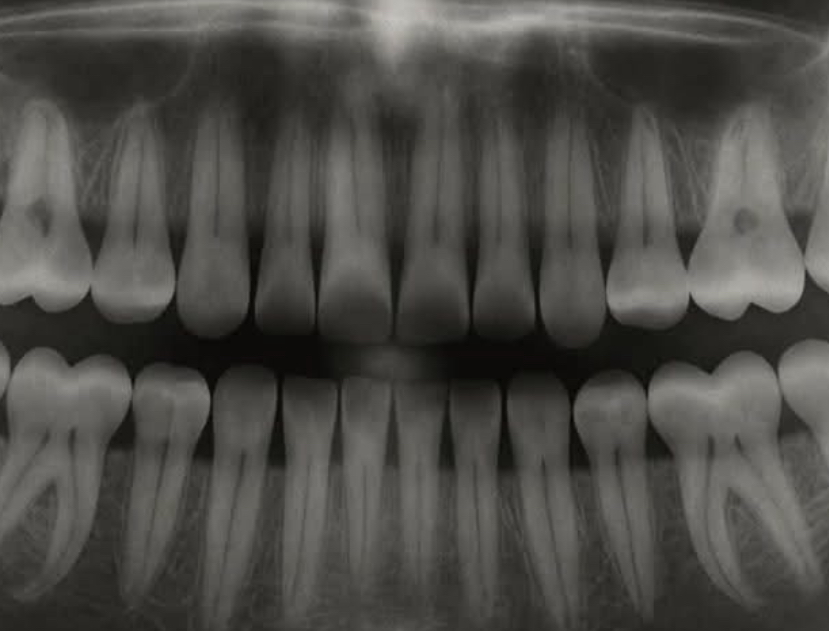

Odontoiatria Giappone: la ricrescita dei denti, la rivoluzione promossa dalla ricerca giapponese – Da sempre la perdita dei denti è stata considerata irreversibile negli esseri umani, con soluzioni come protesi e impianti. Oggi, un team di scienziati giapponesi sta conducendo una sperimentazione clinica su un nuovo farmaco capace di stimolare la ricrescita naturale dei denti, grazie all’inibizione della proteina USAG-1, che agisce come freno alla formazione dentale. Dopo aver completato con successo le fasi precliniche e di sicurezza sugli animali, ora si testano i primi effetti sugli esseri umani, con risultati promettenti e senza effetti collaterali gravi. La ricerca, guidata dal dottor Katsu Takahashi dell’Università di Kyoto, punta a rendere disponibile questa terapia entro il 2030, offrendo una soluzione rivoluzionaria per bambini con malattie genetiche, adulti con denti perduti e chi non può sottoporsi a impianti. Tuttavia, permangono sfide legate alla sicurezza a lungo termine, ai costi e alle normative. Se confermato, questo progresso potrebbe trasformare per sempre l’odontoiatria, rendendo i denti naturali una possibilità concreta e duratura.